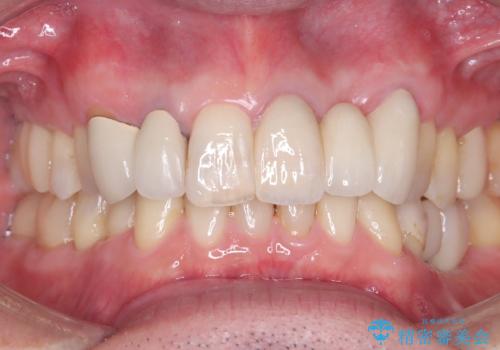

左上3の牽引を1か月半ほど行った後、補綴治療を行っています。

両支台歯とも根尖病巣は認められなかったため、ファイバ-コアからのやり替えとしました。